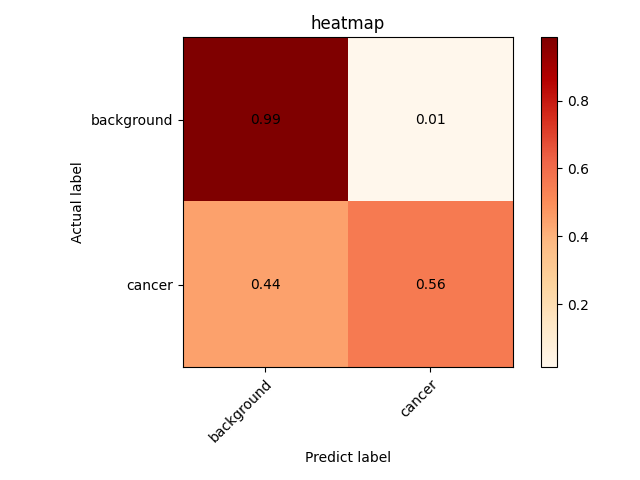

以我们的数据为例,下面是改进模型1得到的结果。